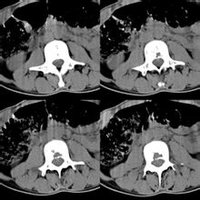

椎管椎管由游離椎骨的椎孔和骶骨的骶管連成,上接枕骨大孔與顱腔相通,下達骶管裂孔而終。其內容有脊髓、脊髓被膜、脊神經根、血管及少量結締組織等。1.椎管壁的構成椎管是一骨纖維性管道,其前壁由椎體後面、椎間盤後緣和後縱韌帶構成,後壁為椎弓板、黃韌帶和關節突關節,兩側壁為椎弓根和椎間孔。椎管骶段由骶椎的椎孔連成,為骨性管道。構成椎管壁的任何結構發生病變,如椎體骨質增生、椎間盤突出以及黃韌帶肥厚等因素均可使椎管腔變形或變狹窄,壓迫其內容物而引起一系列症狀。2.椎管腔的形態在橫斷面觀,各段椎管的形態和大小不完全相同。頸段上部近枕骨大孔處近似圓形,往下為三角形,矢徑短,橫徑長;胸段大致呈圓形;腰段上、中部呈三角形,下部呈三葉形;骶段呈扁三角形。椎管以第4~6胸椎最為狹小,頸段以第7頸椎、腰段以第4腰椎較小。